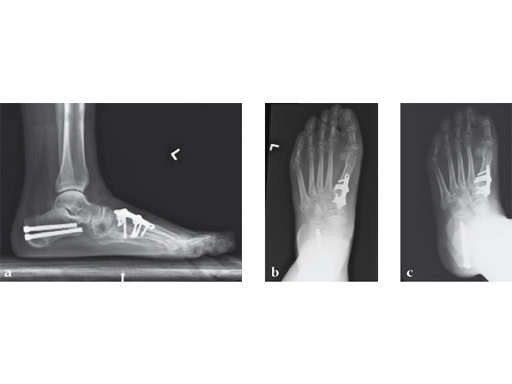

Case 5: First TMT, straight fusion and TMT fusion plates

A 46-year-old obese woman with coronary artery disease had sustained a Lisfranc injury while performing an exercise program. She was unable to weight bear and used an electric scooter.

In an effort to restore her ability to exercise and taking into consideration her body weight and upper extremity weakness, a decision was made to use the variable angle locking compression plate. These postoperative x-rays were obtained at 3 months, one month after beginning weight bearing. The patients pain was reduced and she was able to resume a progressive exercise program after 4 months following surgery.

Case provided by Michael Castro, Scottsdale, Arizona